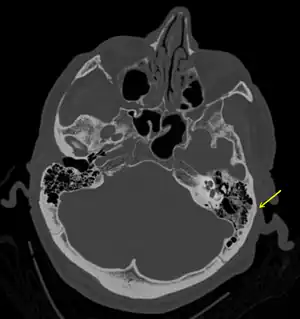

| A subtle temporal bone fracture as seen on CT in a person with a severe head injury | |

Basilar skull fractures include breaks in the posterior skull base or anterior skull base. The former involve the occipital bone, temporal bone, and portions of the sphenoid bone; the latter, superior portions of the sphenoid and ethmoid bones. The temporal bone fracture is encountered in 75% of all basilar skull fractures and may be longitudinal, transverse or mixed, depending on the course of the fracture line in relation to the longitudinal axis of the pyramid.[6]

Temporal bone fractures

Acute injury to the internal carotid artery (carotid dissection, occlusion, pseudoaneurysm formation) may be asymptomatic or result in life-threatening bleeding. They are almost exclusively observed when the carotid canal is fractured, although only a minority of carotid canal fractures result in vascular injury. Involvement of the petrous segment of the carotid canal is associated with a relatively high incidence of carotid injury.[11]